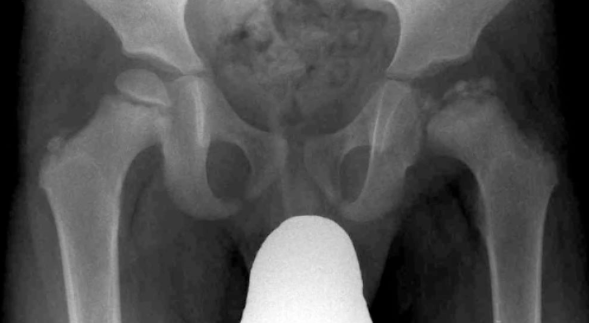

AP and Frog-Leg Lateral Pelvic X-ray: first line, can be normal

Will see sclerosis and fragmentation on hip x-ray

What is Klein's line?

On hip x-ray to diagnose SUFE * Klein’s line drawn along superior border of femoral neck and should intersect with growth plate * Failure to do so suggests early SUFE * Lateral X-ray better at picking this up as most slips posteroinferior